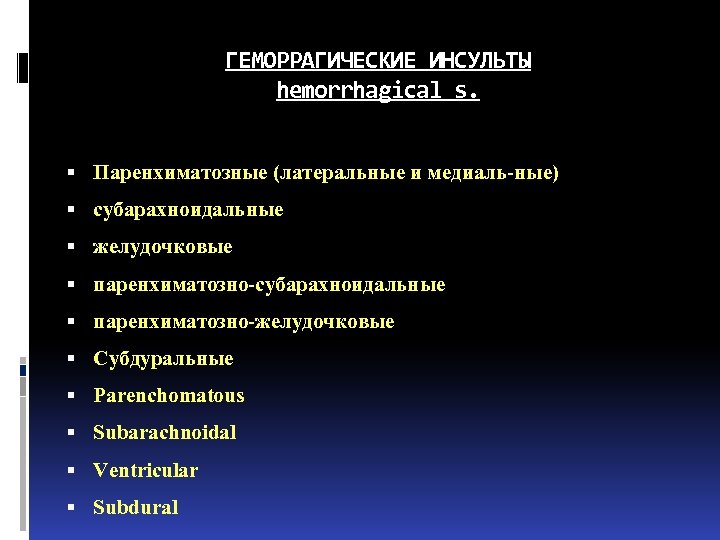

ГЕМОРРАГИЧЕСКИЕ ИНСУЛЬТЫ hemorrhagical s. Паренхиматозные (латеральные и медиаль-ные) субарахноидальные желудочковые паренхиматозно-субарахноидальные паренхиматозно-желудочковые Субдуральные Parenchomatous Subarachnoidal Ventricular Subdural

ГЕМОРРАГИЧЕСКИЕ ИНСУЛЬТЫ hemorrhagical s. Паренхиматозные (латеральные и медиаль-ные) субарахноидальные желудочковые паренхиматозно-субарахноидальные паренхиматозно-желудочковые Субдуральные Parenchomatous Subarachnoidal Ventricular Subdural